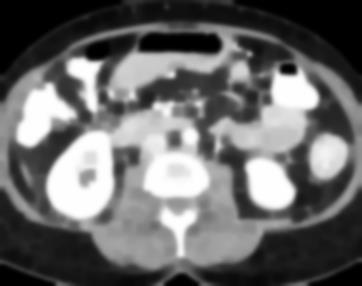

Due to the constraints of the imaging device and high cost in operation time, computer tomography (CT) scans are usually acquired with low intra-slice resolution. Improving the intra-slice resolution is beneficial to the disease diagnosis for both human experts and computer-aided systems. To this end, this paper builds a novel medical slice synthesis to increase the between-slice resolution. Considering that the ground-truth intermediate medical slices are always absent in clinical practice, we introduce the incremental cross-view mutual distillation strategy to accomplish this task in the self-supervised learning manner. Specifically, we model this problem from three different views: slice-wise interpolation from axial view and pixel-wise interpolation from coronal and sagittal views. Under this circumstance, the models learned from different views can distill valuable knowledge to guide the learning processes of each other. We can repeat this process to make the models synthesize intermediate slice data with increasing inter-slice resolution. To demonstrate the effectiveness of the proposed approach, we conduct comprehensive experiments on a large-scale CT dataset. Quantitative and qualitative comparison results show that our method outperforms state-of-the-art algorithms by clear margins.